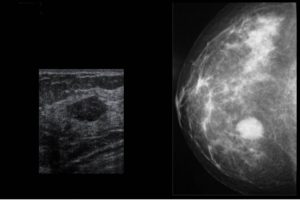

Diplomados en Ultrasonografía